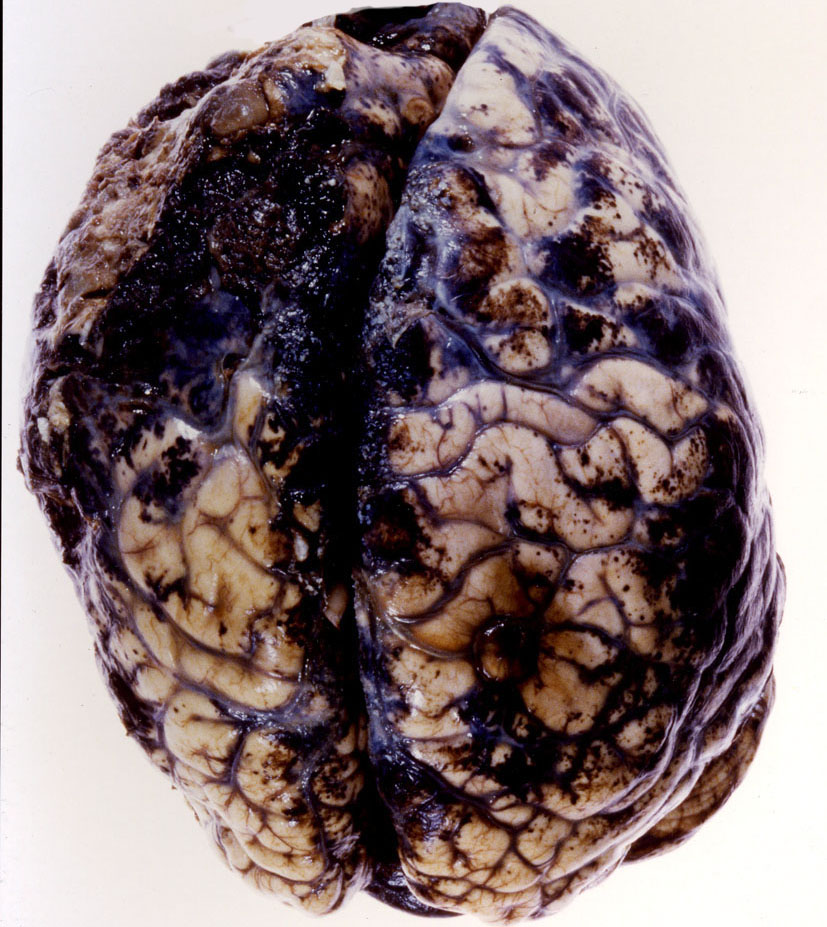

前頭葉の悪性黒色腫で亡くなった13歳の男児の例です。30年以上前ですが,ご許可を得て剖検させていただきました。生まれつき背部から臀部,大腿に大きな有毛性色素性母斑(真っ黒な大きなほくろのようなもので長い毛が生えている)がありました。

剖検脳です,左上が上面から,右上が脳底部から見た写真です。脳底部の軟膜メラノーシスの方が高度です。下の写真は,小脳から延髄のところで切断したものです,小脳表面の脳溝が黒く染まっていて,脳幹部の周囲にもメラニン細胞の増殖があります。よく見ると小脳深部白質や延髄内部にもメラニン色素がみられます。これは悪性黒色腫ではなく軟膜メラノーシスです。悪性黒色腫は左上の写真の前頭葉の部分に発生しました。